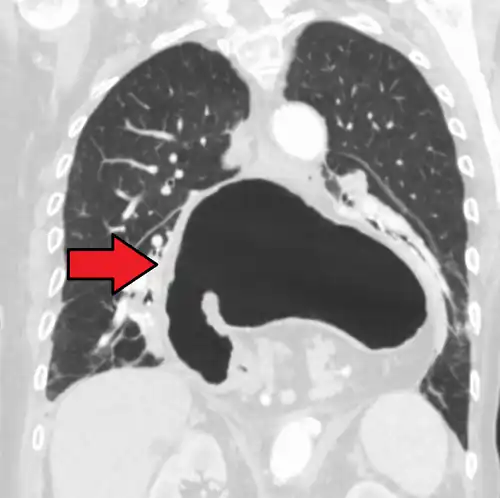

The diagnosis of a hiatal hernia is typically made through an upper GI series, endoscopy, high resolution manometry, esophageal pH monitoring, and computed tomography (CT). Barium swallow, as in the upper GI series, allows the size, location, stricture, and stenosis of oesophagus to be seen. It can also evaluate the oesophageal movements. Endoscopy can analyse the esophageal internal surface for erosions, ulcers, and tumours.

Meanwhile, manometry can determine the integrity of esophageal movements and the presence of esophageal achalasia. pH testing allows the quantitative analysis of acid reflux episodes. A CT scan is useful in diagnosing complications of hiatal hernia, such as gastric volvulus, perforation, pneumoperitoneum, and pneumomediastinum.[8]

Type I: A type I hernia, also known as a sliding hiatal hernia, occurs when part of the stomach slides up through the hiatal opening in the diaphragm.[11] There is a widening of the muscular hiatal tunnel and circumferential laxity of the phrenoesophageal ligament, allowing a portion of the gastric cardia to herniate upward into the posterior mediastinum. The clinical significance of type I hernias is in their association with reflux disease. Sliding hernias are the most common type and account for 95% of all hiatal hernias.[12] (C)

Type II: A type II hernia, also known as a paraesophageal or rolling hernia, occurs when the fundus and greater curvature of the stomach roll up through the diaphragm, forming a pocket alongside the esophagus.[11] It results from a localized defect in the phrenoesophageal ligament while the gastroesophageal junction remains fixed to the preaortic fascia and the median arcuate ligament. The gastric fundus then serves as the leading point of herniation. Although type II hernias are associated with reflux disease, their primary clinical significance lies in the potential for mechanical complications. (D)